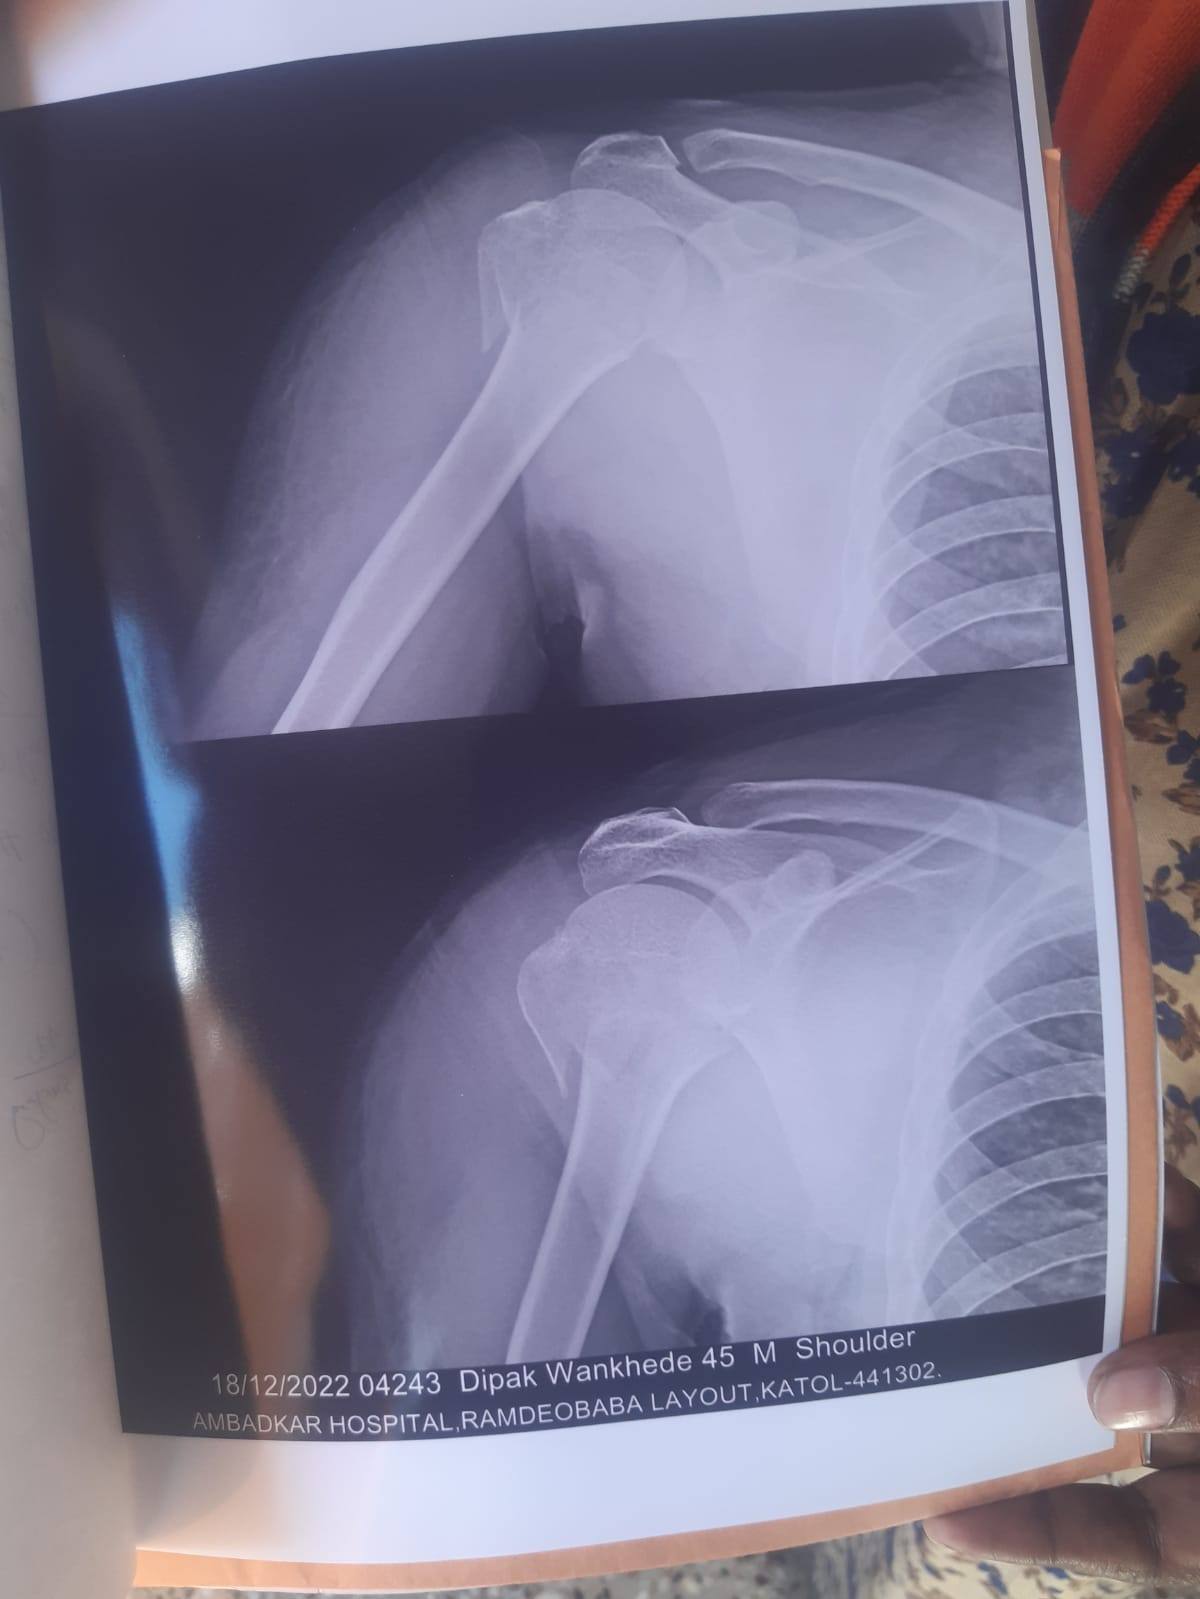

sir mera frakcher bina surgary thik hoga kya

mai surgary nahi karna chahta

1 mhina bit gaya sir movment dhire dhire achhi ho rahi hai per kande me dard hota hai

surgery karwana achha option rahega warna movement sahee nahee ayega